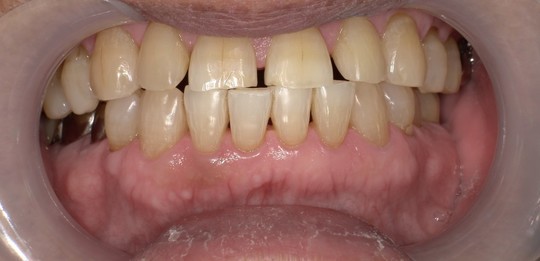

ステイン除去

BEFORE

AFTER

年齢:70代男性

治療内容:エアーフローによる歯の着色汚れ、ステイン除去

治療期間/通院回数:1回

費用: ステインコース 8,800円